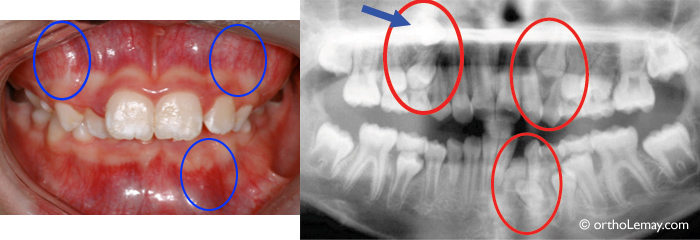

Chevauchement important aux 2 arcades chez une jeune fille de 9 ans. Des extractions sélectives (canines temporaires indiquées par des astérisques *) permettront de désencombrer les dents antérieures et d’aider les problèmes d’éruption qui affecteront les autres dents permanentes.

La radiographie panoramique de cette fille de 10 ans permet de déceler plusieurs problèmes d’éruption (encerclés) pour lesquels il est indiqué d’intervenir. L’extraction de dents temporaires peut aider à changer la direction d’éruption anormale des dents permanentes.